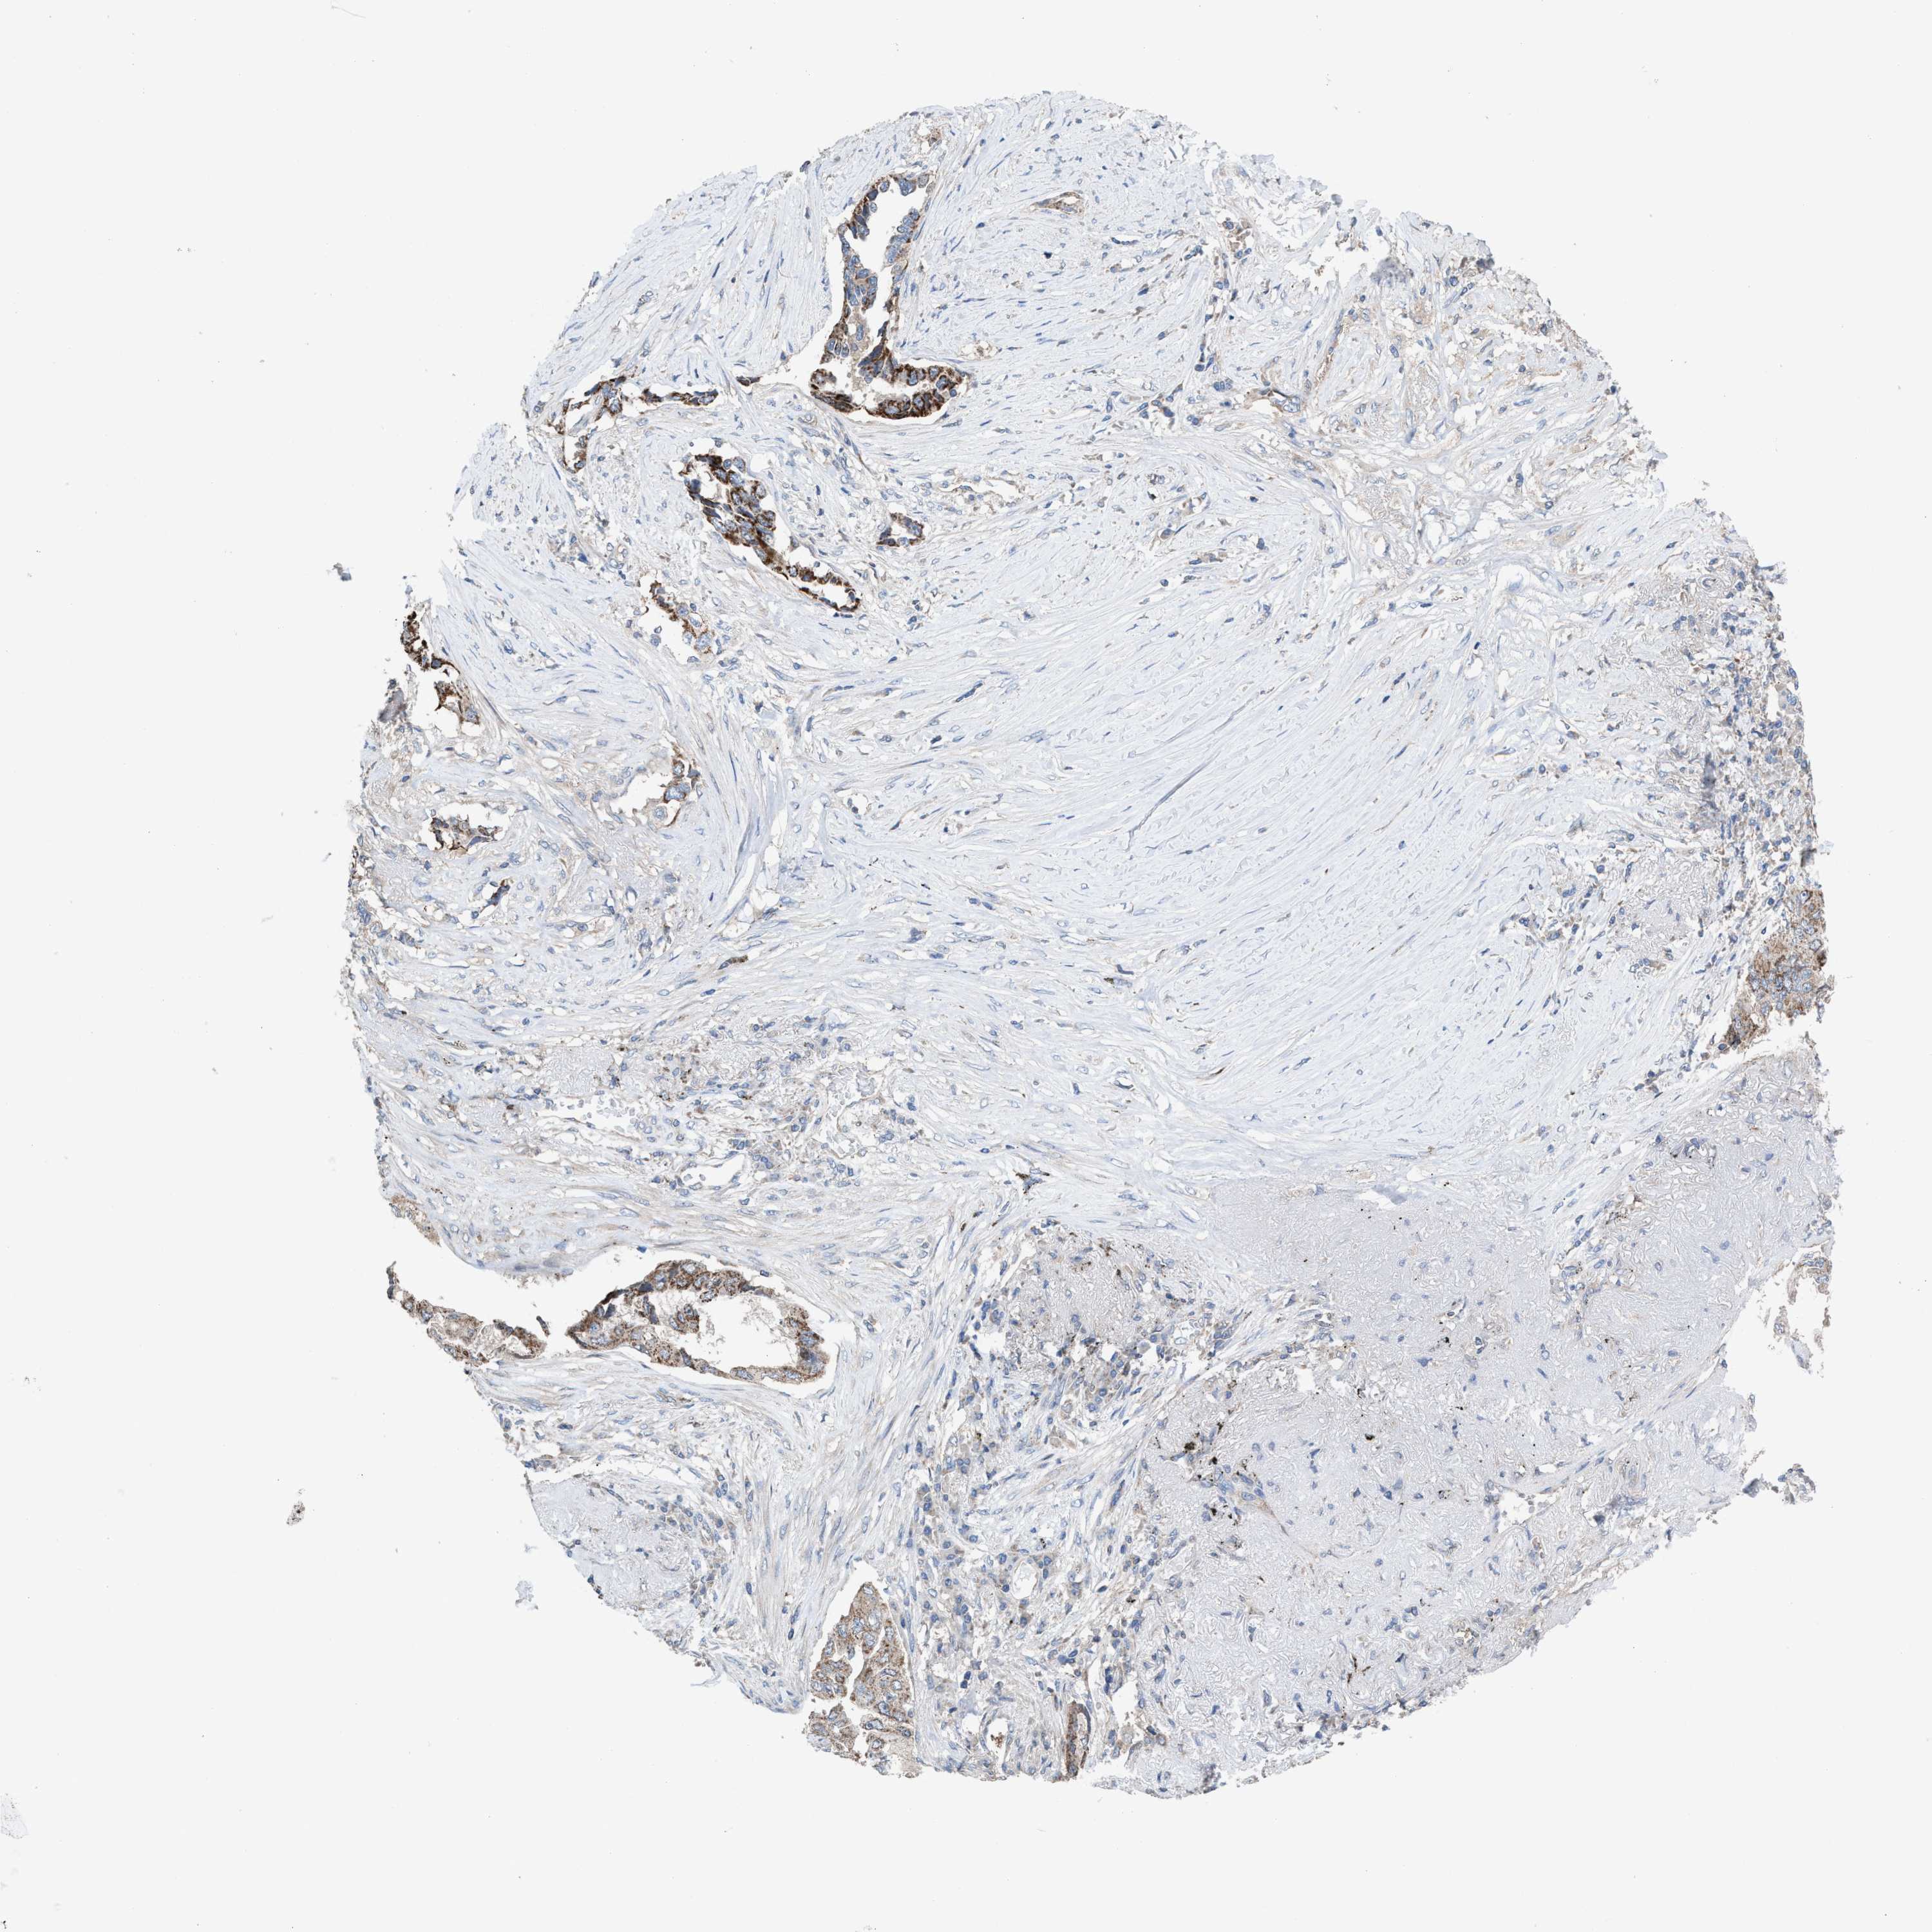

CANCER LUNG CANCER Show tissue menu

LUAD TCGA LUAD VALIDATION LUSC TCGA LUSC VALIDATION PROTEIN LUAD CPTAC PROTEIN LUSC CPTAC PROTEIN EXPRESSION

ANTIBODIES

AND

VALIDATION